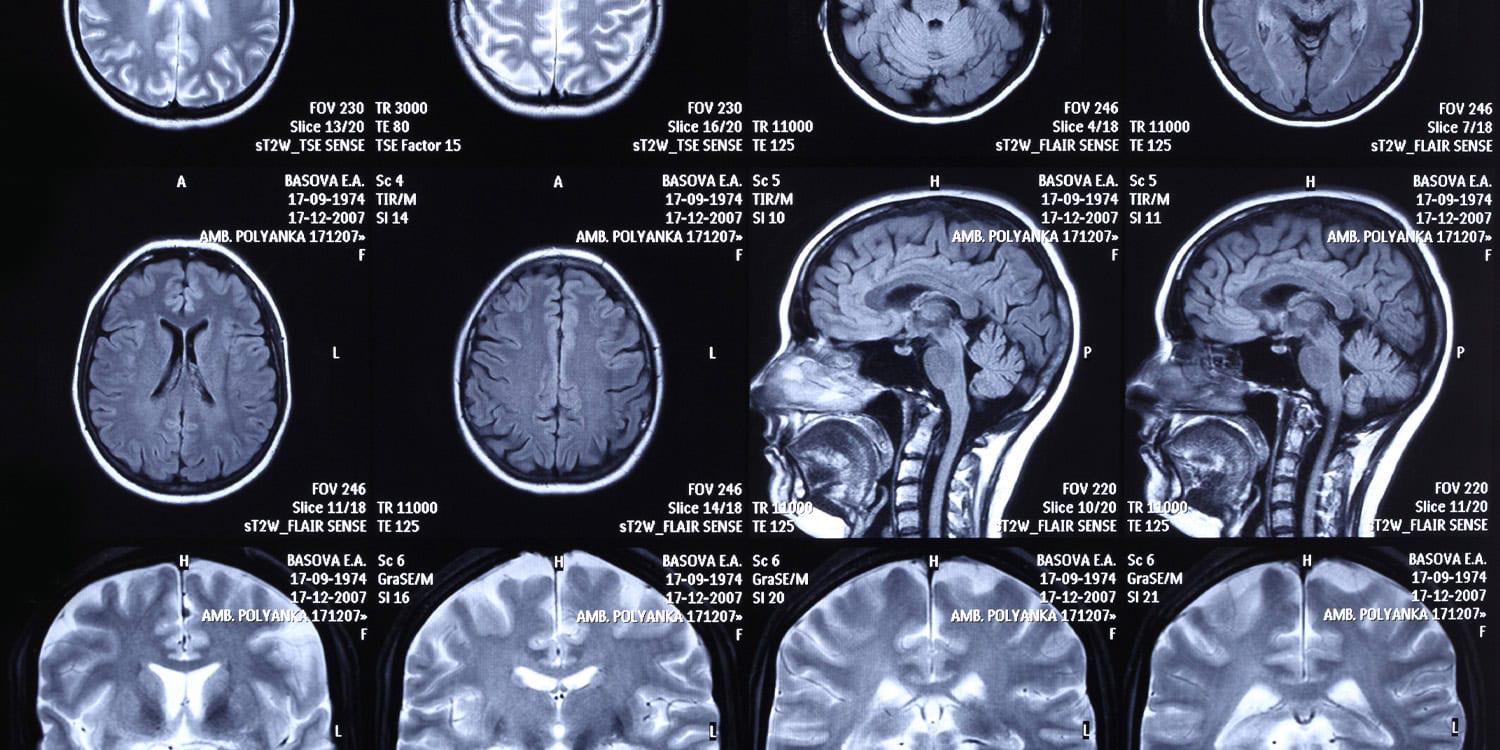

Gehirnscans zeigen, dass Demokraten und Republikaner unterschiedliche Nervenbahnen nutzen, um Lebensmittel einzukaufen. Diese Erkenntnis stammt aus einer in der Fachzeitschrift Politics and the Life Sciences veröffentlichten Neuroimaging-Studie, die ergab, dass Menschen mit unterschiedlichen politischen Zugehörigkeiten auf unterschiedliche Nervenbahnen angewiesen sind

Brain scans reveal Democrats and Republicans use different neural pathways to buy groceries